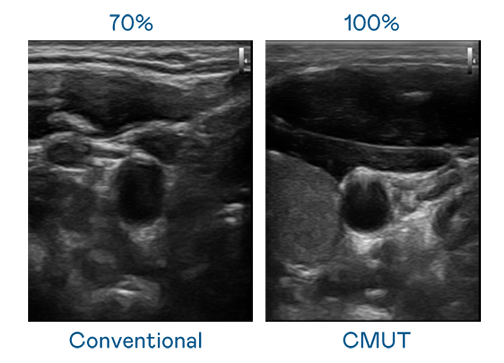

CMUT 技術是一種用電容式微機電元件來產生超音波訊號的技術。與傳統 PZT 壓電式技術相比,CMUT 頻寬增加 30%,更寬頻的超音波訊號讓影像解析度大幅提升,是實現高影像品質醫療超音波掃描、促進精準醫療發展的關鍵技術。

大頻寬帶來超清晰影像

超音波影像的解析度高低,首先取決於探頭能發出的訊號頻寬。冰球突破 CMUT 可提供高清晰的超音波訊號,提供高頻寬、高靈敏度、影像紋理細節更高的超音波影像,協助醫護人員縮短影像判讀時間及利用精準的醫療影像進行診斷。